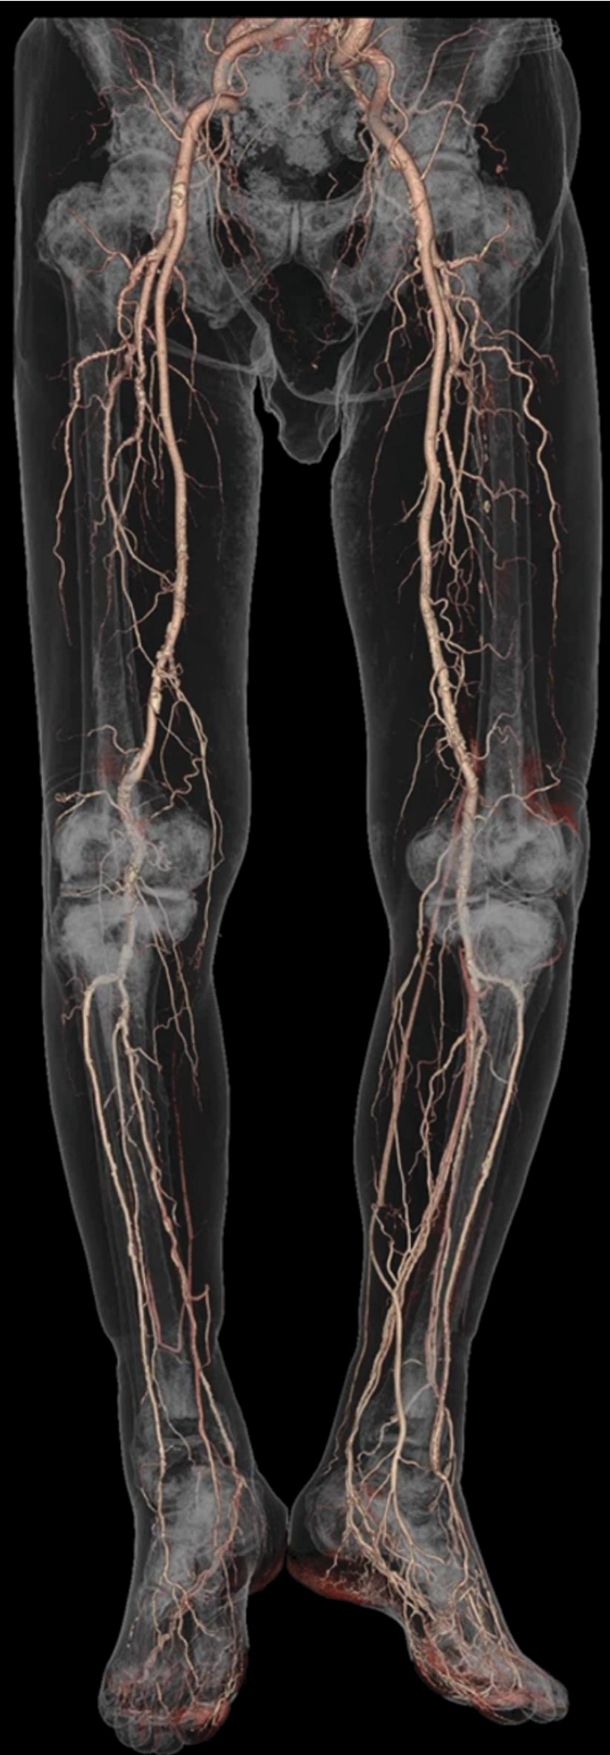

Computed tomography (CT) uses thousands of x-ray transmission measurements taken at different angles around a patient to produce three-dimensional cross-sectional images of the human body. That technology allows physicians to visualize their patients’ internal anatomy, as shown in the opening image, and reveals the presence of acute and chronic diseases and the consequences of injury in remarkable detail. Prior to the integration of CT into clinical radiology, physicians relied on exploratory surgery to diagnose many serious patient symptoms. Thankfully, that’s now a relic of the past.

The physical dimensions measured in CT data sets are also quantitatively accurate. That’s a result of the well-defined geometry required in CT, in which all transmission measurements are made along straight lines between the x-ray source and detector elements. Because of that geometry, radiation-based cancer treatments can be accurately planned and performed; biopsy needles can be accurately positioned; and linear, areal, and volumetric measurements can be accurately made. For example, the correct size for a stent to be placed in a patient’s artery can be determined by the measurement of the diameter of the artery on the CT image. The volume of a tumor can be assessed by outlining its 3D boundaries, and a patient’s response to radiation or drug therapy can be deduced by measuring changes in tumor volume over time.